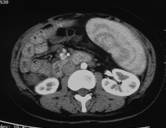

赵×,女,31岁,病毒性肝炎肝硬化伴脾亢。术前CT增强(图1a~图1c)见脾脏显著增大,外周血常规示:白细胞1.24×109/L;血小板40×109/L;红细胞2.15×1012/L。行“超选择分级栓塞脾动脉”介入手术治疗(图2a~图2b),术后3月复查外周血常规示:白细胞3.65×109/L;血小板130×109/L;红细胞2.59×1012/L。

图1a 图1b 图1c

图2a 图2b